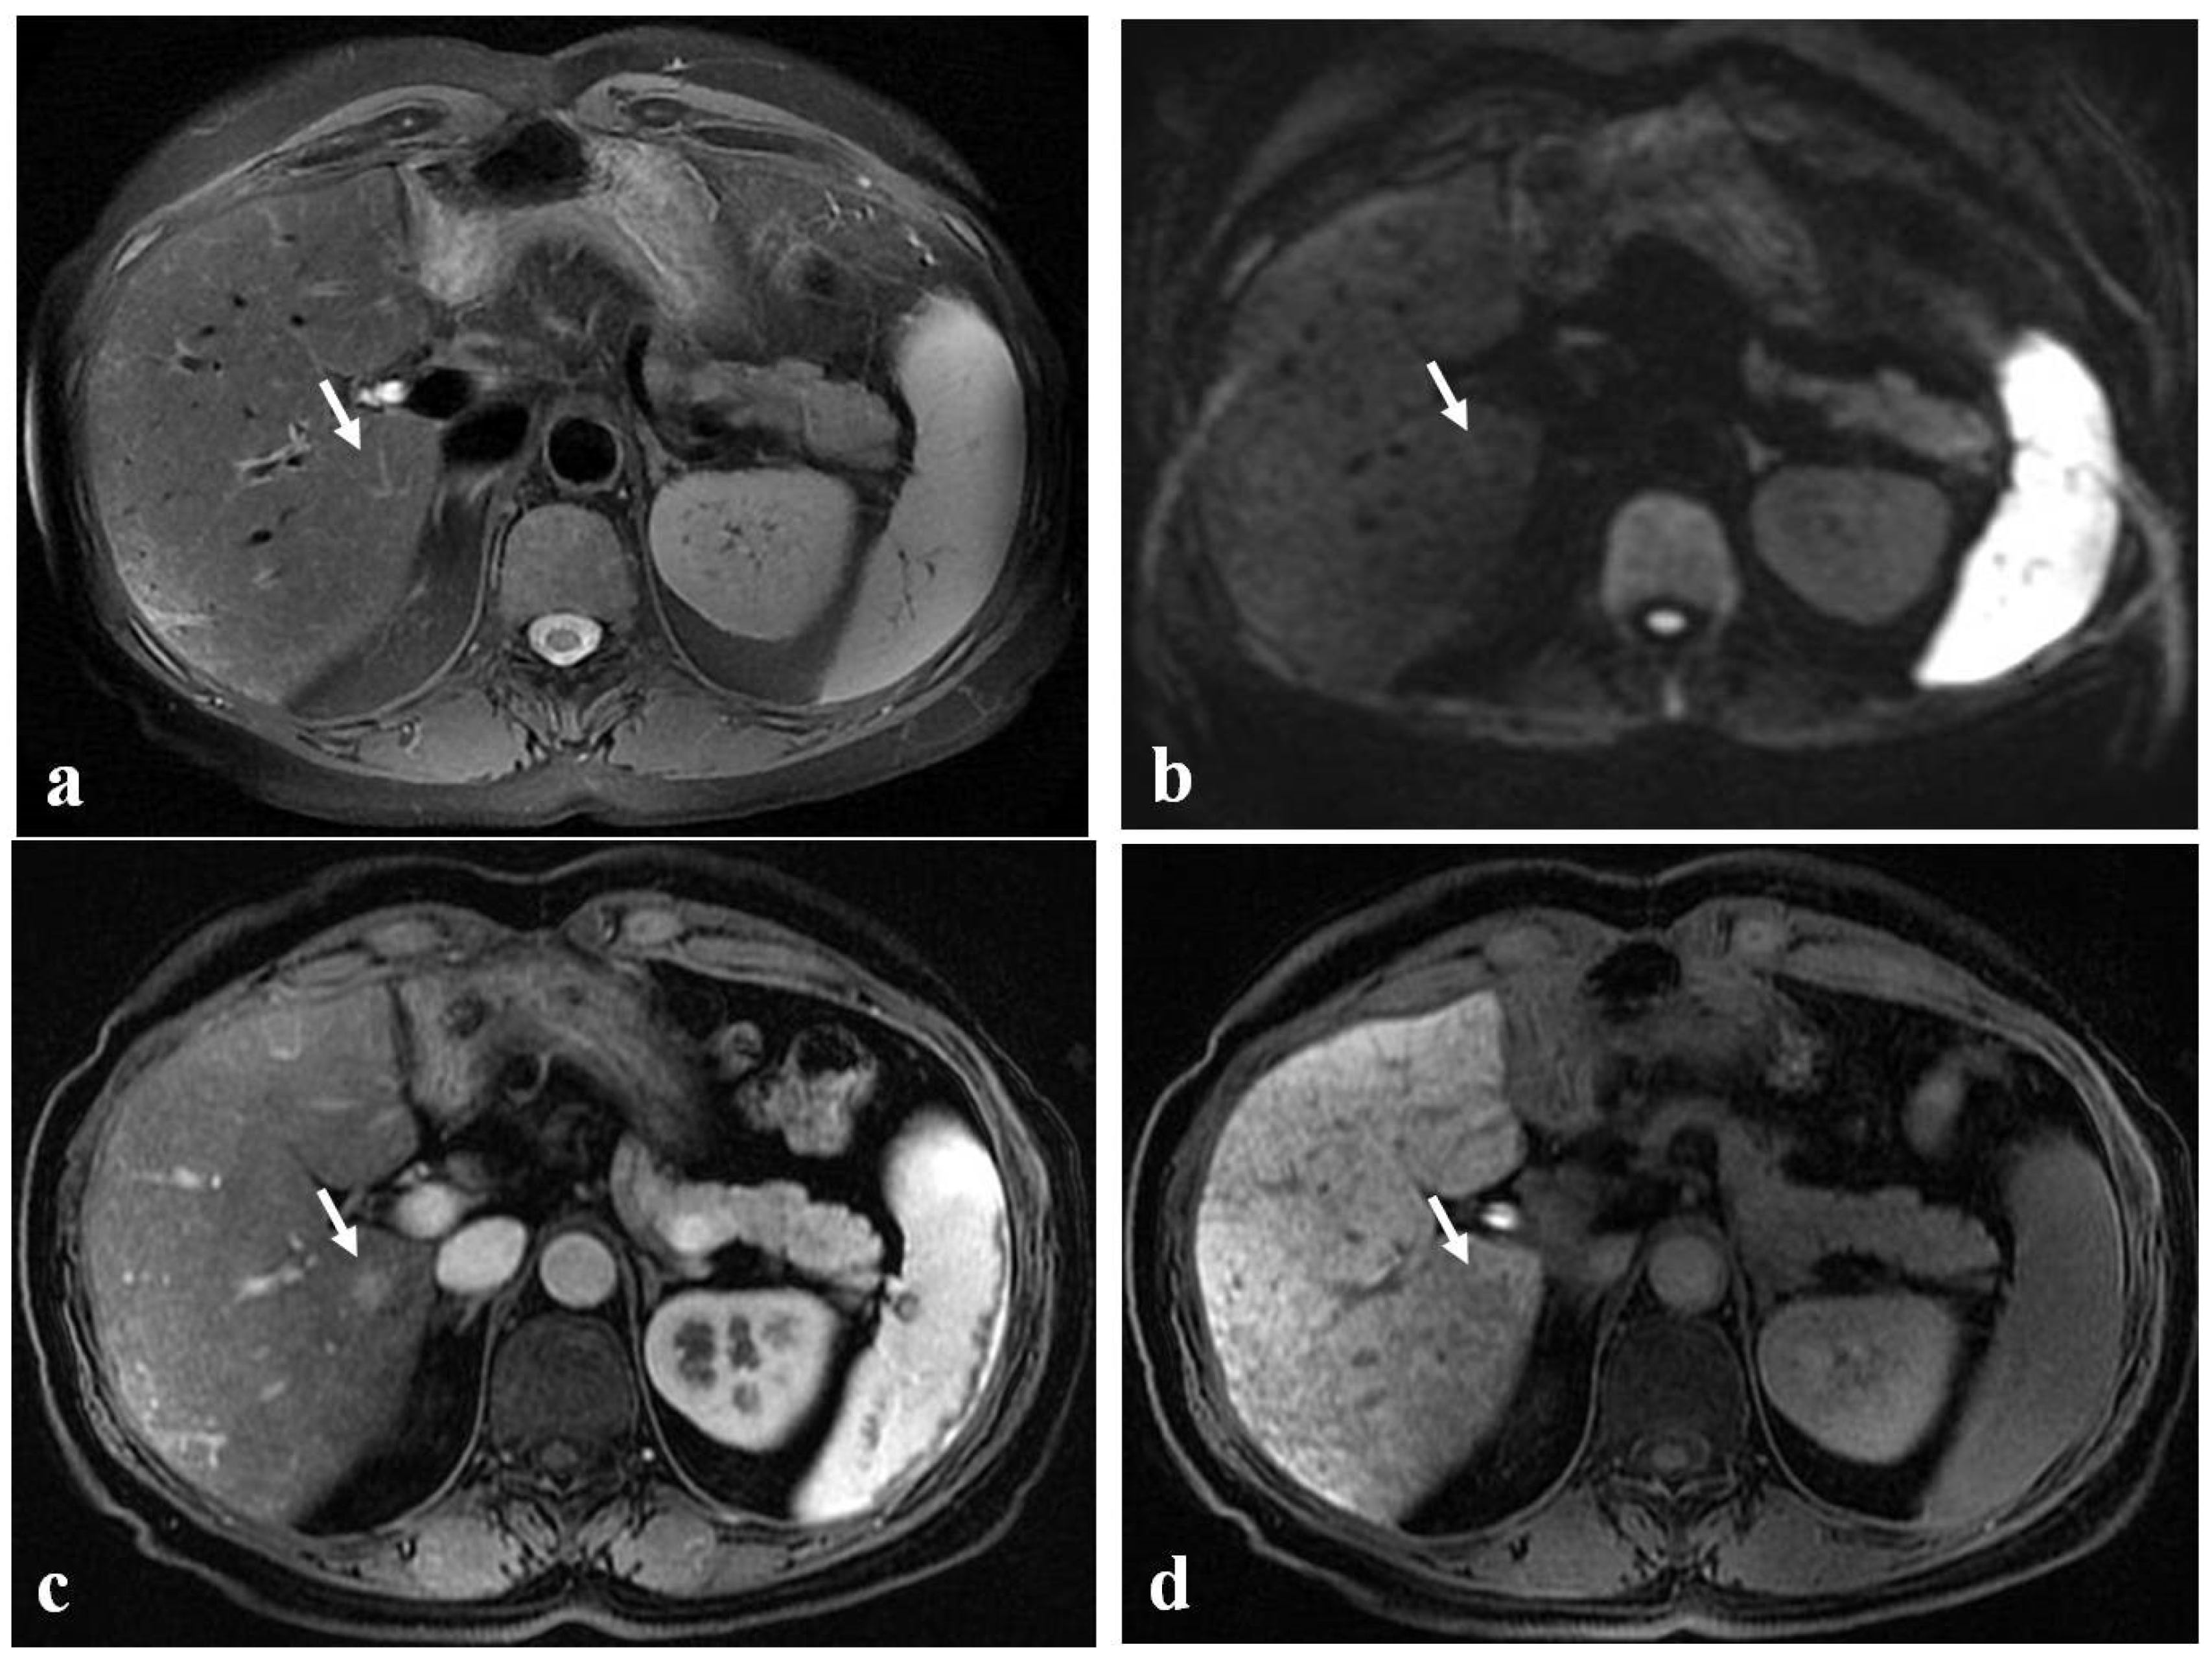

- Han, N.Y.; Park, B.J.; Sung, D.J.; Kim, M.J.; Cho, S.B.; Lee, C.H.; Jang, Y.J.; Kim, S.Y.; Kim, D.S.; Um, S.H.; et al. Chemotherapy-induced focal hepatopathy in patients with gastrointestinal malignancy: Gadoxetic acid–enhanced and diffusion-weighted MR imaging with clinical-pathologic correlation. Radiology 2014, 271, 416–425. [Google Scholar] [CrossRef]